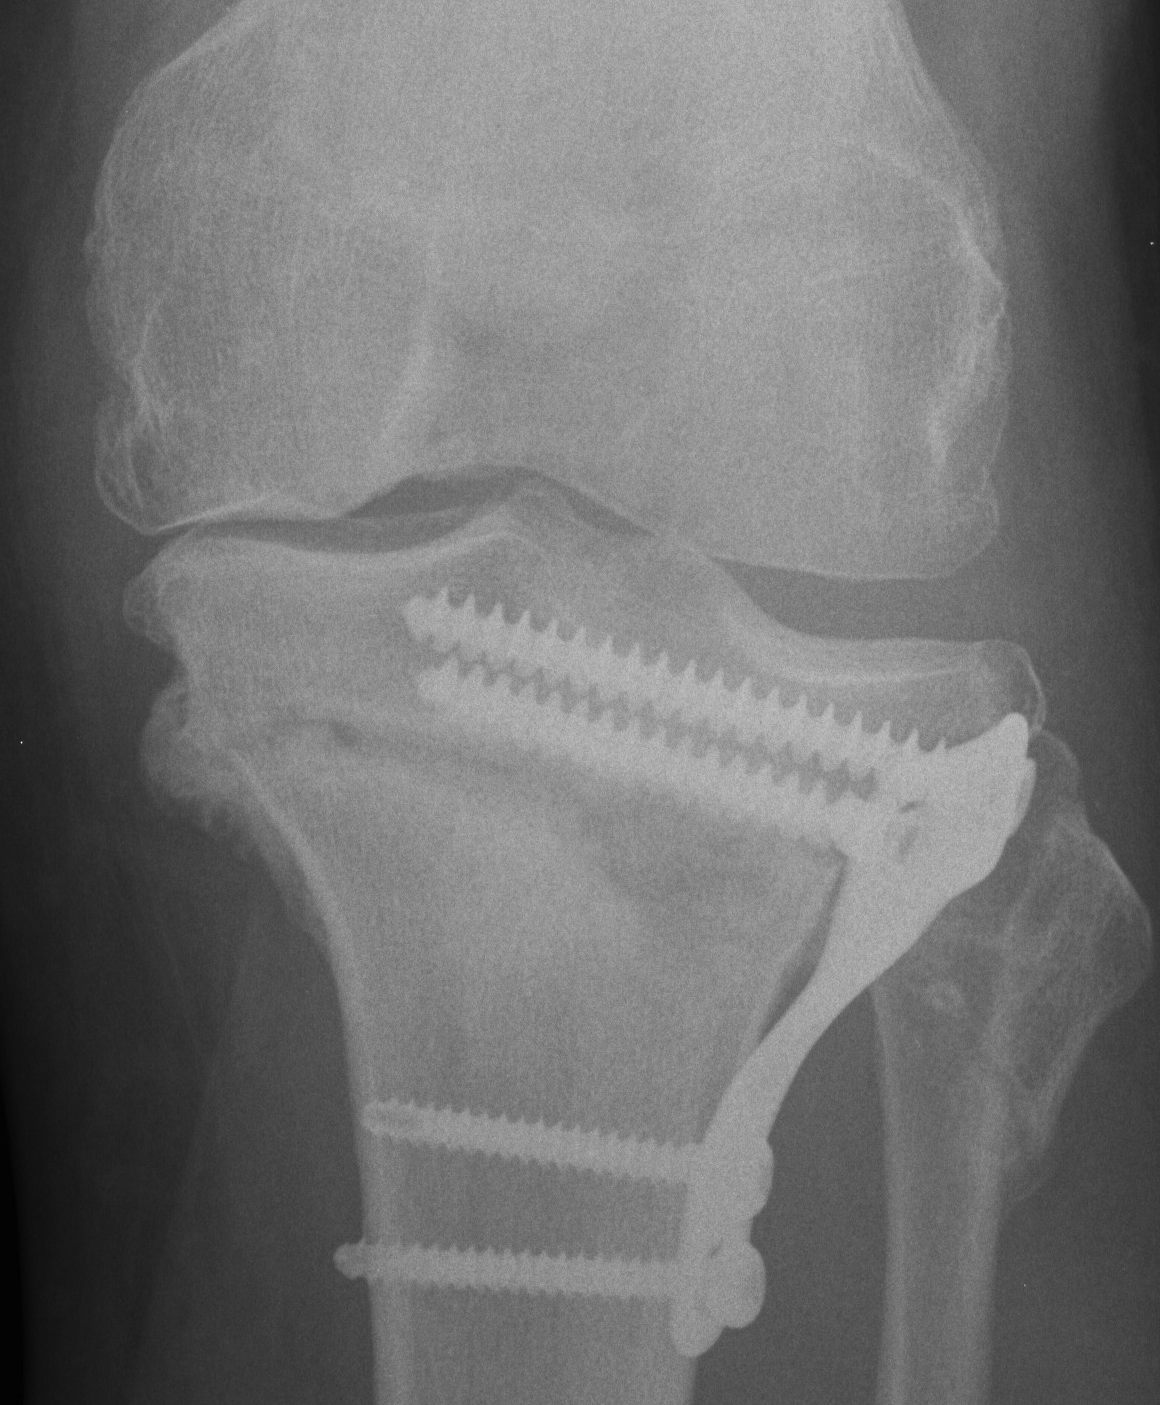

Medial hinge fracture

van Raaij et al Acta Orthop 2008

- 44 closing wedge HTO

- 36/44 (82%) had fracture

- no significant malunion